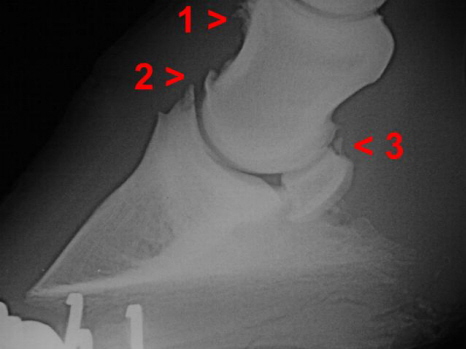

Arthrose Hufgelenk